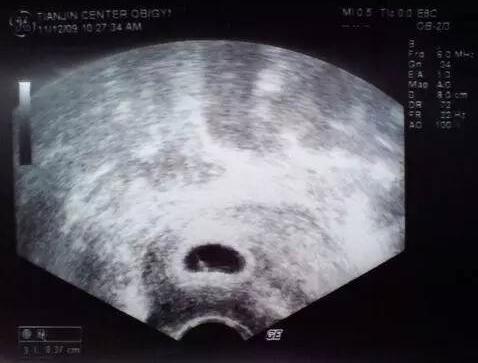

一般来说,一个正常发育的坯胎,是30-40天形成胎囊,在40-50天形成胎芽,最后的话是在50-60天的时候就能看看胎儿的胎心了,所以建议各位准妈妈在怀孕60天的时候再去做b超,这个时候就能全面的看见胎儿的孕囊、胎芽以及胎心了。